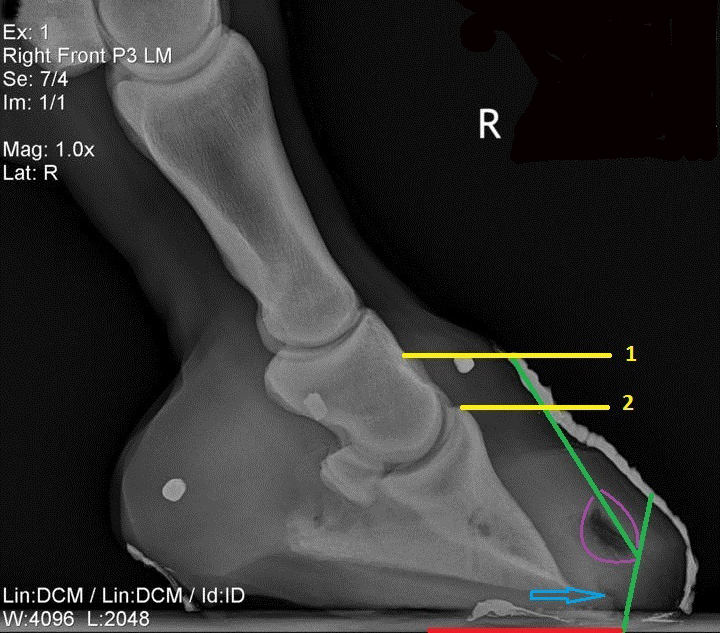

It is critical to trim a laminitic foot to a normal alignment of the hoof capsule and the internal structures with the aid of radiographs. If radiographs show coffin bone rotation or descent, the horse will need a realigning trim. The purpose is (1) to relieve abnormal forces that would do even more damage; and (2) to encourage correct hoof wall growth. This involves the trimming required to make the hoof wall parallel with the edge of the coffin bone again, realigning the structures. Over time, internal structures that work for the horse for healthy blood perfusion and energy dissipation may be restored.

If the amount of rotation or descent is not severe, a realigning trim can often be done simply by backing up the toe through the white line. If that does not fully correct the hoof wall/coffin bone alignment, the toe can be beveled so that the point of break-over at the toe lines up with where the hoof wall should be to correspond with the new position of the coffin bone. The bottom of the coffin bone should be sitting no more than 5 degrees above a ground-parallel position.